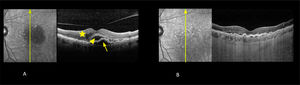

Degeneración macular asociada a la edad neovascular (DMAEn)

Fotografía infrarroja y tomografía de coherencia óptica de dominio espectral (OCT).

A Pre tratamiento. Agudeza visual de 0,5. Se observa acumulación de líquido en los espacios subepitelio pigmentario (flecha), subretinal (cabeza de flecha) e intrarretinal (estrella) al OCT.

B. Post tratamiento con aflibercept respuesta inicial después de 3 inyecciones mensuales. Agudeza visual 1,0 parcial. Se observa reabsorción casi total del líquido en los espacios subepitelio pigmentario, subretinal e intrarretinal.